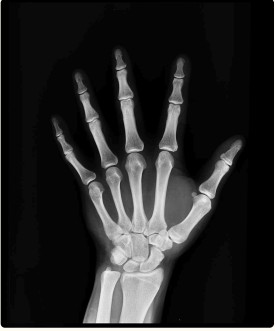

There are six small bones in the wrist that interlock like small dice that all have different shapes. Together, they make all the various movements of your wrist possible.

These small bones are called “carpals”, hence the carpal from carpal tunnel.

On the inside of your wrist (palm side), these bones come together in such a way to make a tunnel into the palm and hand. Inside of this tunnel are tendons for the muscles of your fingers, arteries and veins to provide blood flow, and a very important nerve called the median nerve.